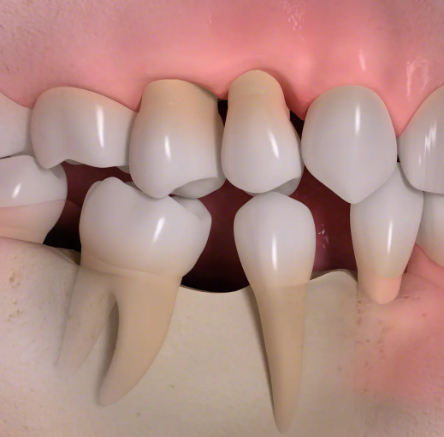

歯を失ったままにしておくと、以下のような見た目・機能・精神面での悪影響が広がっていきます:

■骨が吸収され、歯ぐきが痩せて老けて見える

■隣の歯や噛み合う歯が移動し、噛み合わせが悪くなる

■噛める歯が減り、食事を楽しめなくなる

歯を失ったままにしておくと

• 1

歯根が失われると、骨に伝わる力がなくなり、歯を失った部分の骨がやせていきます。

• 2

歯の喪失によって歯が移動し、歯並びがかわってしまう場合があります。

• 3

歯の喪失によって、見た目が悪くなります。

• 4

骨の喪失によって顔の輪郭が変わってしまいます。